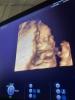

покидайте пожалуйста фотки 4d со 2скрининга 🫶🏼интересно посмотреть🥹

или 3d

я думала это и есть 4d

оказывается это 3d🌝